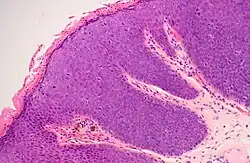

Intraepithelial neoplasia

Intraepithelial neoplasia (IEN) is the development of a benign neoplasia or high-grade dysplasia in an epithelium. The exact dividing line between dysplasia and neoplasia has been very difficult to draw throughout the era of medical science. It varies between persons. In the localizations shown below, the term intraepithelial neoplasia is used to describe more accurately what was historically referred to as epithelial dysplasia. IEN is not cancer, but it is associated with higher risk for developing cancer in future. It is thus sometimes a precancerous condition.